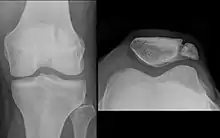

In this X-ray, an anatomical variation of the patella can be seen – the bipartate patella, in which the patella is split into two parts.

Emarginations (i.e. patella emarginata, a "missing piece") are common laterally on the proximal edge.[1] Bipartite patellas are the result of an ossification of a second cartilaginous layer at the location of an emargination. Previously, bipartite patellas were explained as the failure of several ossification centres to fuse, but this idea has been rejected. Partite patellas occur almost exclusively in men. Tripartite and even multipartite patellas occur.